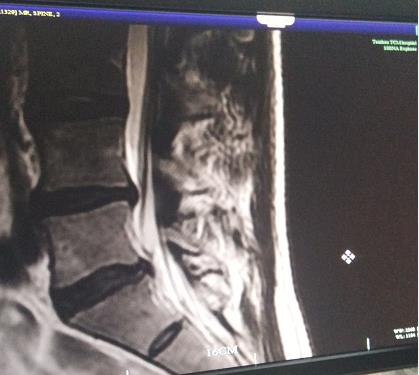

去年,张先生的检查报告上报纸黑字地写着:L4/L5椎间盘向后偏左局限性突出,硬膜囊受压变形,左神经根受压移位。L3/L4、L5/S1椎间盘未见明显异常重象,椎体边缘见骨质增生。